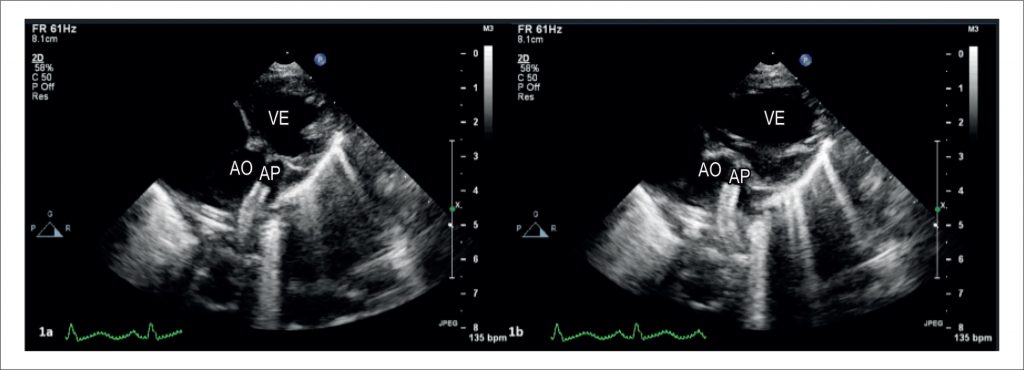

IMAGEM

Stent Ductal Oscilante na Atresia Pulmonar Valvar

Arun Gopalakrishnan et al.